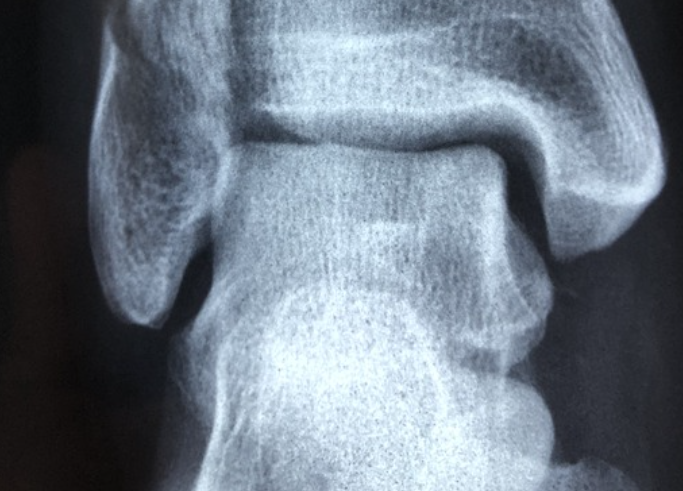

골다공증이란 말 그대로 뼈에 다공(구멍)이 생긴 상태를 말합니다. 이는 뼈의 양이 감소하고 강도도 약해져서 일상의 작은 충격에도 쉽게 부러질 수 있기 때문에 많은 주의가 필요한 질병입니다.

뼈가 가지는 특성으로 인해 질환 초기에는 특별한 증상이 나타나지 않습니다. 초기 증상으로는 척추뼈가 약해져 휘거나 압착되어 키가 줄어들 수 있습니다.

골절의 위험도 증가합니다. 심한 경우 물건을 들려고 허리를 구부리거나 기침을 하는 와중에도 쉽게 뼈가 부러지기도 합니다.

골다공증은 남성에 비해 여성이 약 15배가 많이 발생하며 50대 이상에서 증가하는 질환입니다. 50~70대 여성은 주로 손목 골절이 나타나고 70대 이상의 경우 고관절이나 척추의 골절이 흔하게 발생됩니다.

진단

골다공증은 골밀도를 측정하여 확인되는 T-값을 활용하여 진단합니다. 수치가 -1 이상이면 정상, -1에서 -2.5 사이이면 골감소증, -2.5 이하인 경우 골다공증으로 분류합니다.